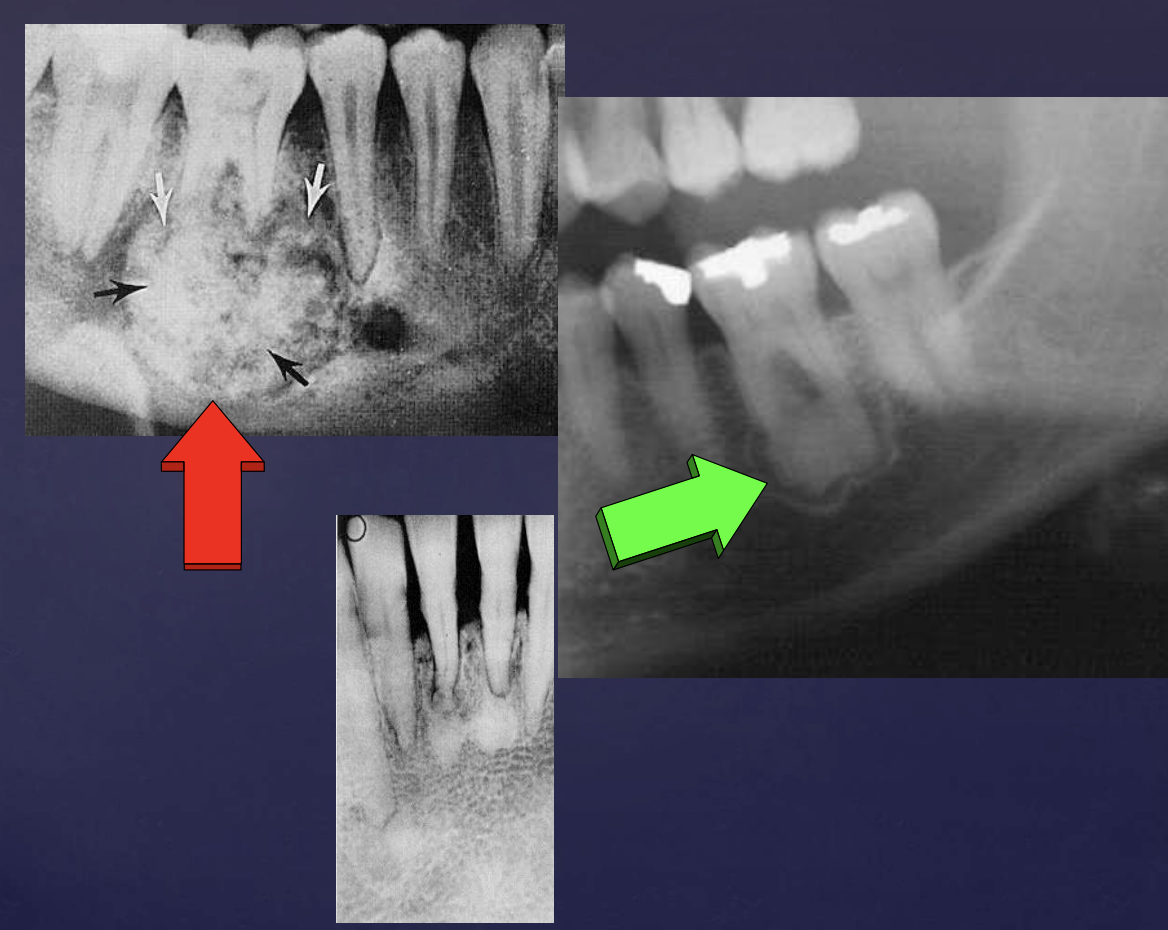

how do ameloblastomas radiographically present?

well circumscribed, corticated

radiolucent

unilocular/multilocular (coarse/curved septae)

expansile

Tooth displacement/root resorption

ameloblastomas

ameloblastoma

Pericoronal/mural; impacted tooth

Displacement of #32

Osseous expansion

Thinning of cortices

Displacement of inferior alveolar nerve canal

Multilocular

Root resorption

Thinning of inferior mandibular border

Septae appear coarse

Displacement of teeth